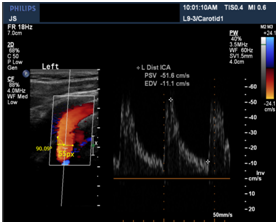

PSV is the Peak Systolic Velocity obtained from the Dicom images and considered as real part of the peak to peak value in the above graph similar to the denominator of ‘amp’. Here after, we mention only the PSV values.

Similar to the above ultrasound image, 5 images at different points in CCA, ICA, and ECA respectively of the same patient were taken. And velocities at the points L2, L5 and L3 were calculated given velocities at L1 and L4 with ±5% errors based on the flow rate division with different Windkessel models stitched along the artery with the calculated radius from the images and assuming an average elasticity, thickness, viscosities and densities of the blood (Figure 7).

Table 2 Compares the velocities obtained by Simulation (Est. velocity) and the observed velocities from Ultrasound image of ECA of the same patient as tabulated in Table 1

Est. Velocity at L3 (cm/s)

Observed Velocity at L3

Error